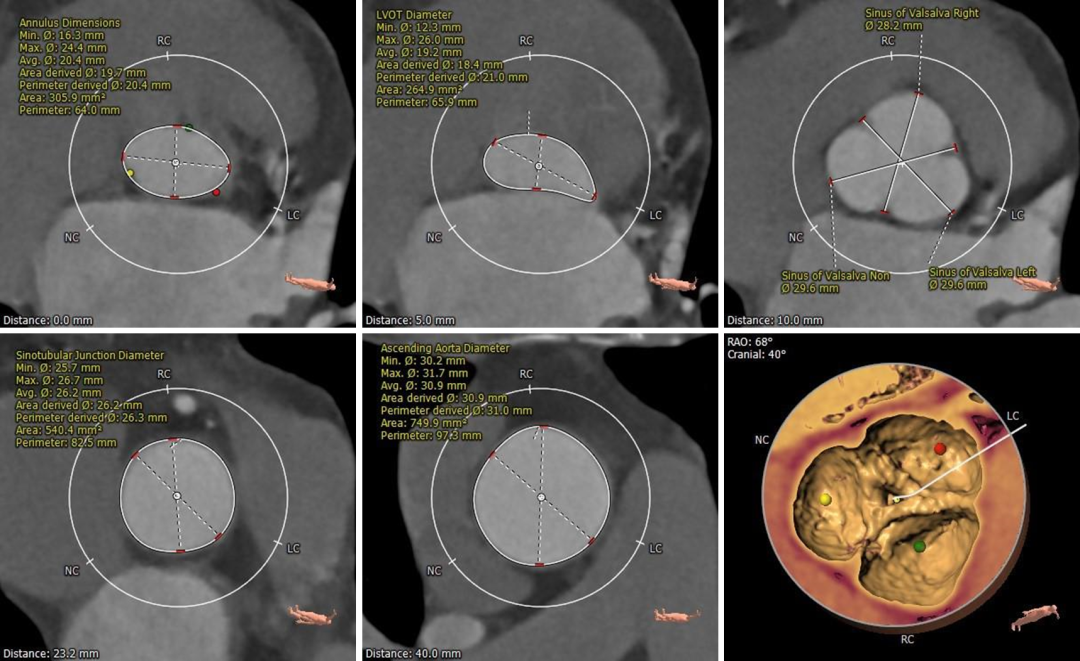

根部测量

三叶式瓣,瓣叶增厚黏连,无钙化

冠脉高度

冠脉开口高度可,未见冗长瓣叶

左室测量

左室心肌肥厚